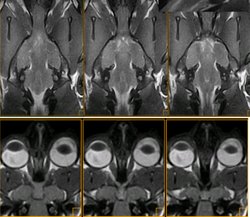

Detalle del quisma óptico de un gato (imagen de resonancia magnética)